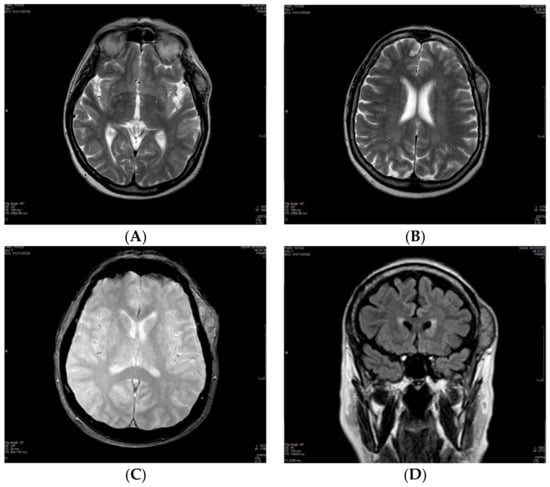

| 20 October 2021 | MRI of the brain: single 2.5 × 5 cm soft tissue temporal lesion. Suspected benign lesion. |